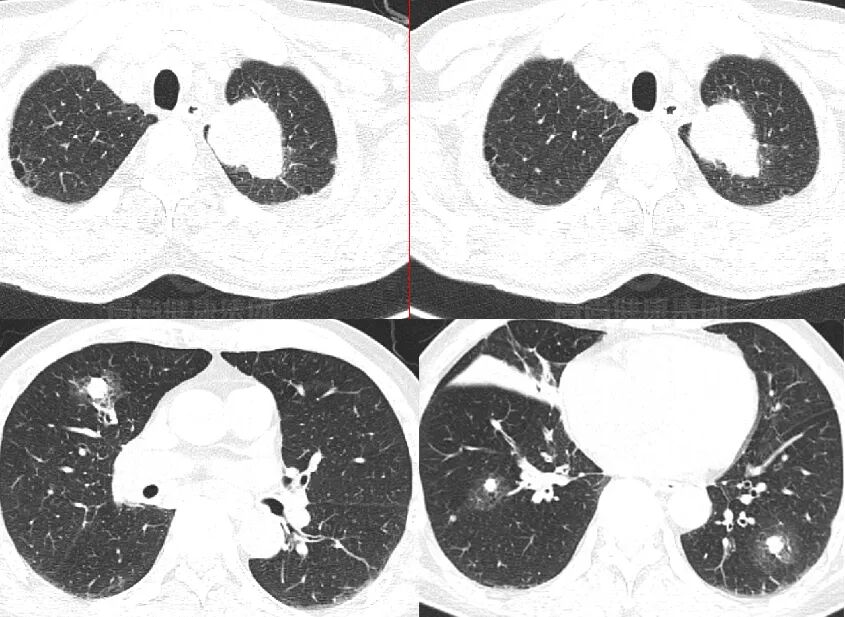

PET/CT 图像

纤支镜病理

肺腺癌(高分化)。

PET/CT 表现

双肺多发斑片状实变影,内充气支气管征,部分囊状扩张,FDG 摄取不均匀增高,SUVmax5.1

右下肺病灶穿刺病理

黏膜相关淋巴组织结外边缘区淋巴瘤(MALT 淋巴瘤)

病例 5

描述

PET/CT 显像全身多发高代谢病变,左上肺癌伴肺、骨广泛转移。